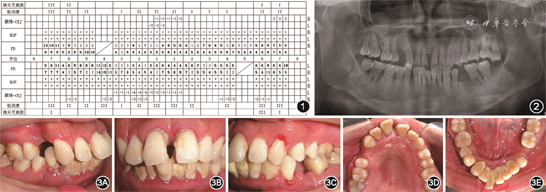

(2)临床及影像学检查:全口口腔卫生差,软垢指数为3,牙石(+++);全口牙龈充血红肿,质地松软,局部位点自发性出血;全口探诊出血(bleeding on probing,BOP)阳性位点百分比为100%(156/156),全口探诊深度(probing depth,PD)2~14 mm,其中PD≥5 mm的位点占64.1%(100/156),临床附着丧失(clinical attachment loss,CAL)2~14 mm;17、31、36、37、41、44、47Ⅲ度松动,多颗牙Ⅰ~Ⅱ度松动;17、36根分叉病变Ⅲ度,16根分叉病变Ⅱ度,26、27、37、47根分叉病变Ⅰ度(图1)。全口曲面体层X线片示全口牙槽骨吸收至根长的1/2至2/3,17、36、31、41、44牙槽骨吸收近根尖(图2)。14、35缺失,44、28伸长;上前牙扇形移位,11与21间隙约4 mm,前牙Ⅲ度深覆

、Ⅱ度深覆盖,双侧磨牙中性关系(图3)。